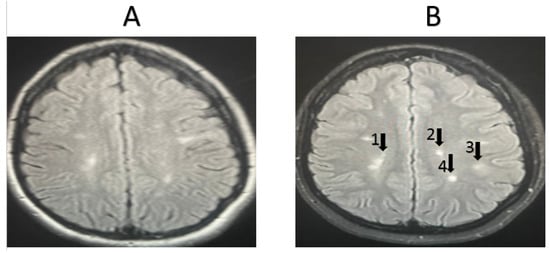

3.2. Magnetic Resonance Imaging Results